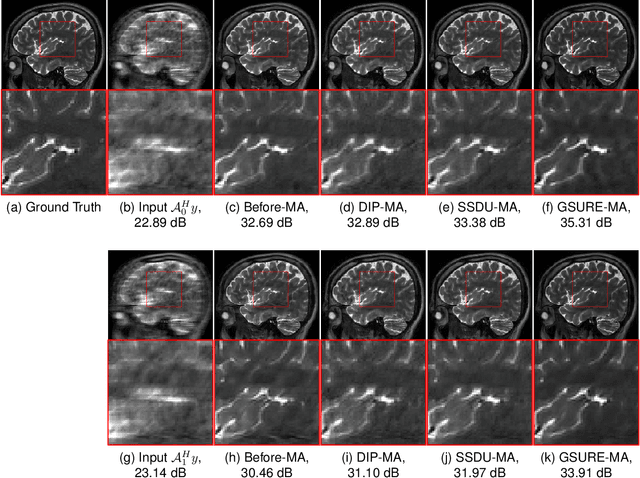

Abstract:Deep learning algorithms that rely on extensive training data are revolutionizing image recovery from ill-posed measurements. Training data is scarce in many imaging applications, including ultra-high-resolution imaging. The deep image prior (DIP) algorithm was introduced for single-shot image recovery, completely eliminating the need for training data. A challenge with this scheme is the need for early stopping to minimize the overfitting of the CNN parameters to the noise in the measurements. We introduce a generalized Stein's unbiased risk estimate (GSURE) loss metric to minimize the overfitting. Our experiments show that the SURE-DIP approach minimizes the overfitting issues, thus offering significantly improved performance over classical DIP schemes. We also use the SURE-DIP approach with model-based unrolling architectures, which offers improved performance over direct inversion schemes.

Abstract:Deep learning image reconstruction algorithms often suffer from model mismatches when the acquisition scheme differs significantly from the forward model used during training. We introduce a Generalized Stein's Unbiased Risk Estimate (GSURE) loss metric to adapt the network to the measured k-space data and minimize model misfit impact. Unlike current methods that rely on the mean square error in kspace, the proposed metric accounts for noise in the measurements. This makes the approach less vulnerable to overfitting, thus offering improved reconstruction quality compared to schemes that rely on mean-square error. This approach may be useful to rapidly adapt pre-trained models to new acquisition settings (e.g., multi-site) and different contrasts than training data

Abstract:Deep learning accelerates the MR image reconstruction process after offline training of a deep neural network from a large volume of clean and fully sampled data. Unfortunately, fully sampled images may not be available or are difficult to acquire in several application areas such as high-resolution imaging. Previous studies have utilized Stein's Unbiased Risk Estimator (SURE) as a mean square error (MSE) estimate for the image denoising problem. Unrolled reconstruction algorithms, where the denoiser at each iteration is trained using SURE, has also been introduced. Unfortunately, the end-to-end training of a network using SURE remains challenging since the projected SURE loss is a poor approximation to the MSE, especially in the heavily undersampled setting. We propose an ENsemble SURE (ENSURE) approach to train a deep network only from undersampled measurements. In particular, we show that training a network using an ensemble of images, each acquired with a different sampling pattern, can closely approximate the MSE. Our preliminary experimental results show that the proposed ENSURE approach gives comparable reconstruction quality to supervised learning and a recent unsupervised learning method.